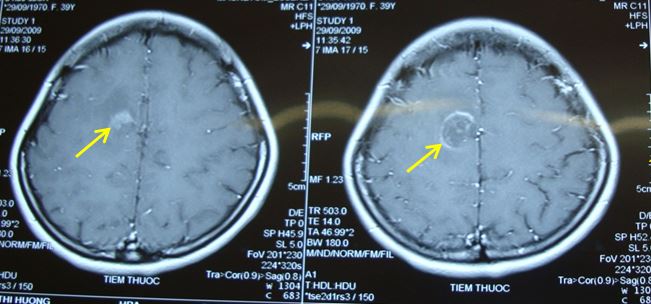

Bệnh nhân đã đến khám tại Bệnh viện Bạch Mai, chụp cộng hưởng từ sọ não phát hiện u não vùng đỉnh phải kích thước 2,5 x 3 cm, có phù não xung quanh và ngấm thuốc mạnh. Trên xung cộng hưởng từ phổ chất chuyển hóa Cholin tăng

Hình ảnh khối u trên phim cộng hưởng từ trước điều trị